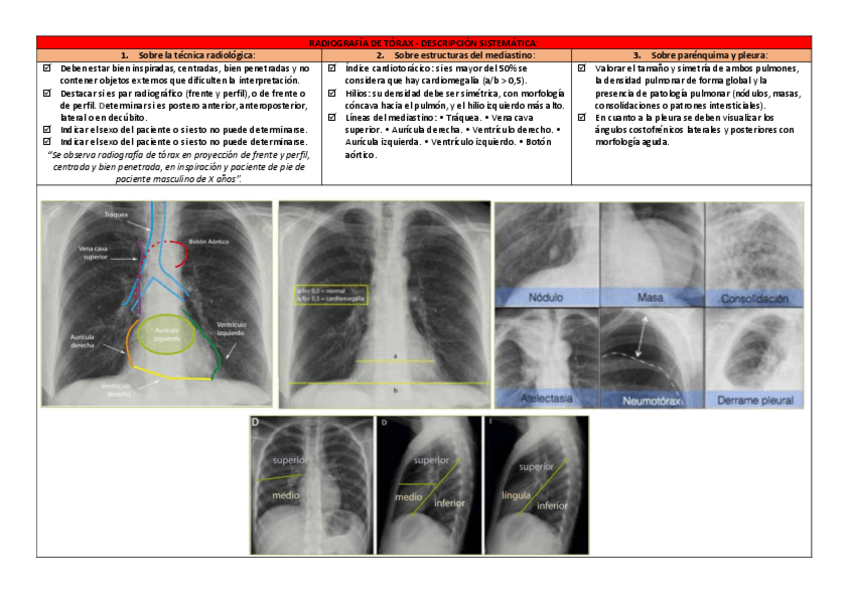

RX.pdf

8 páginas